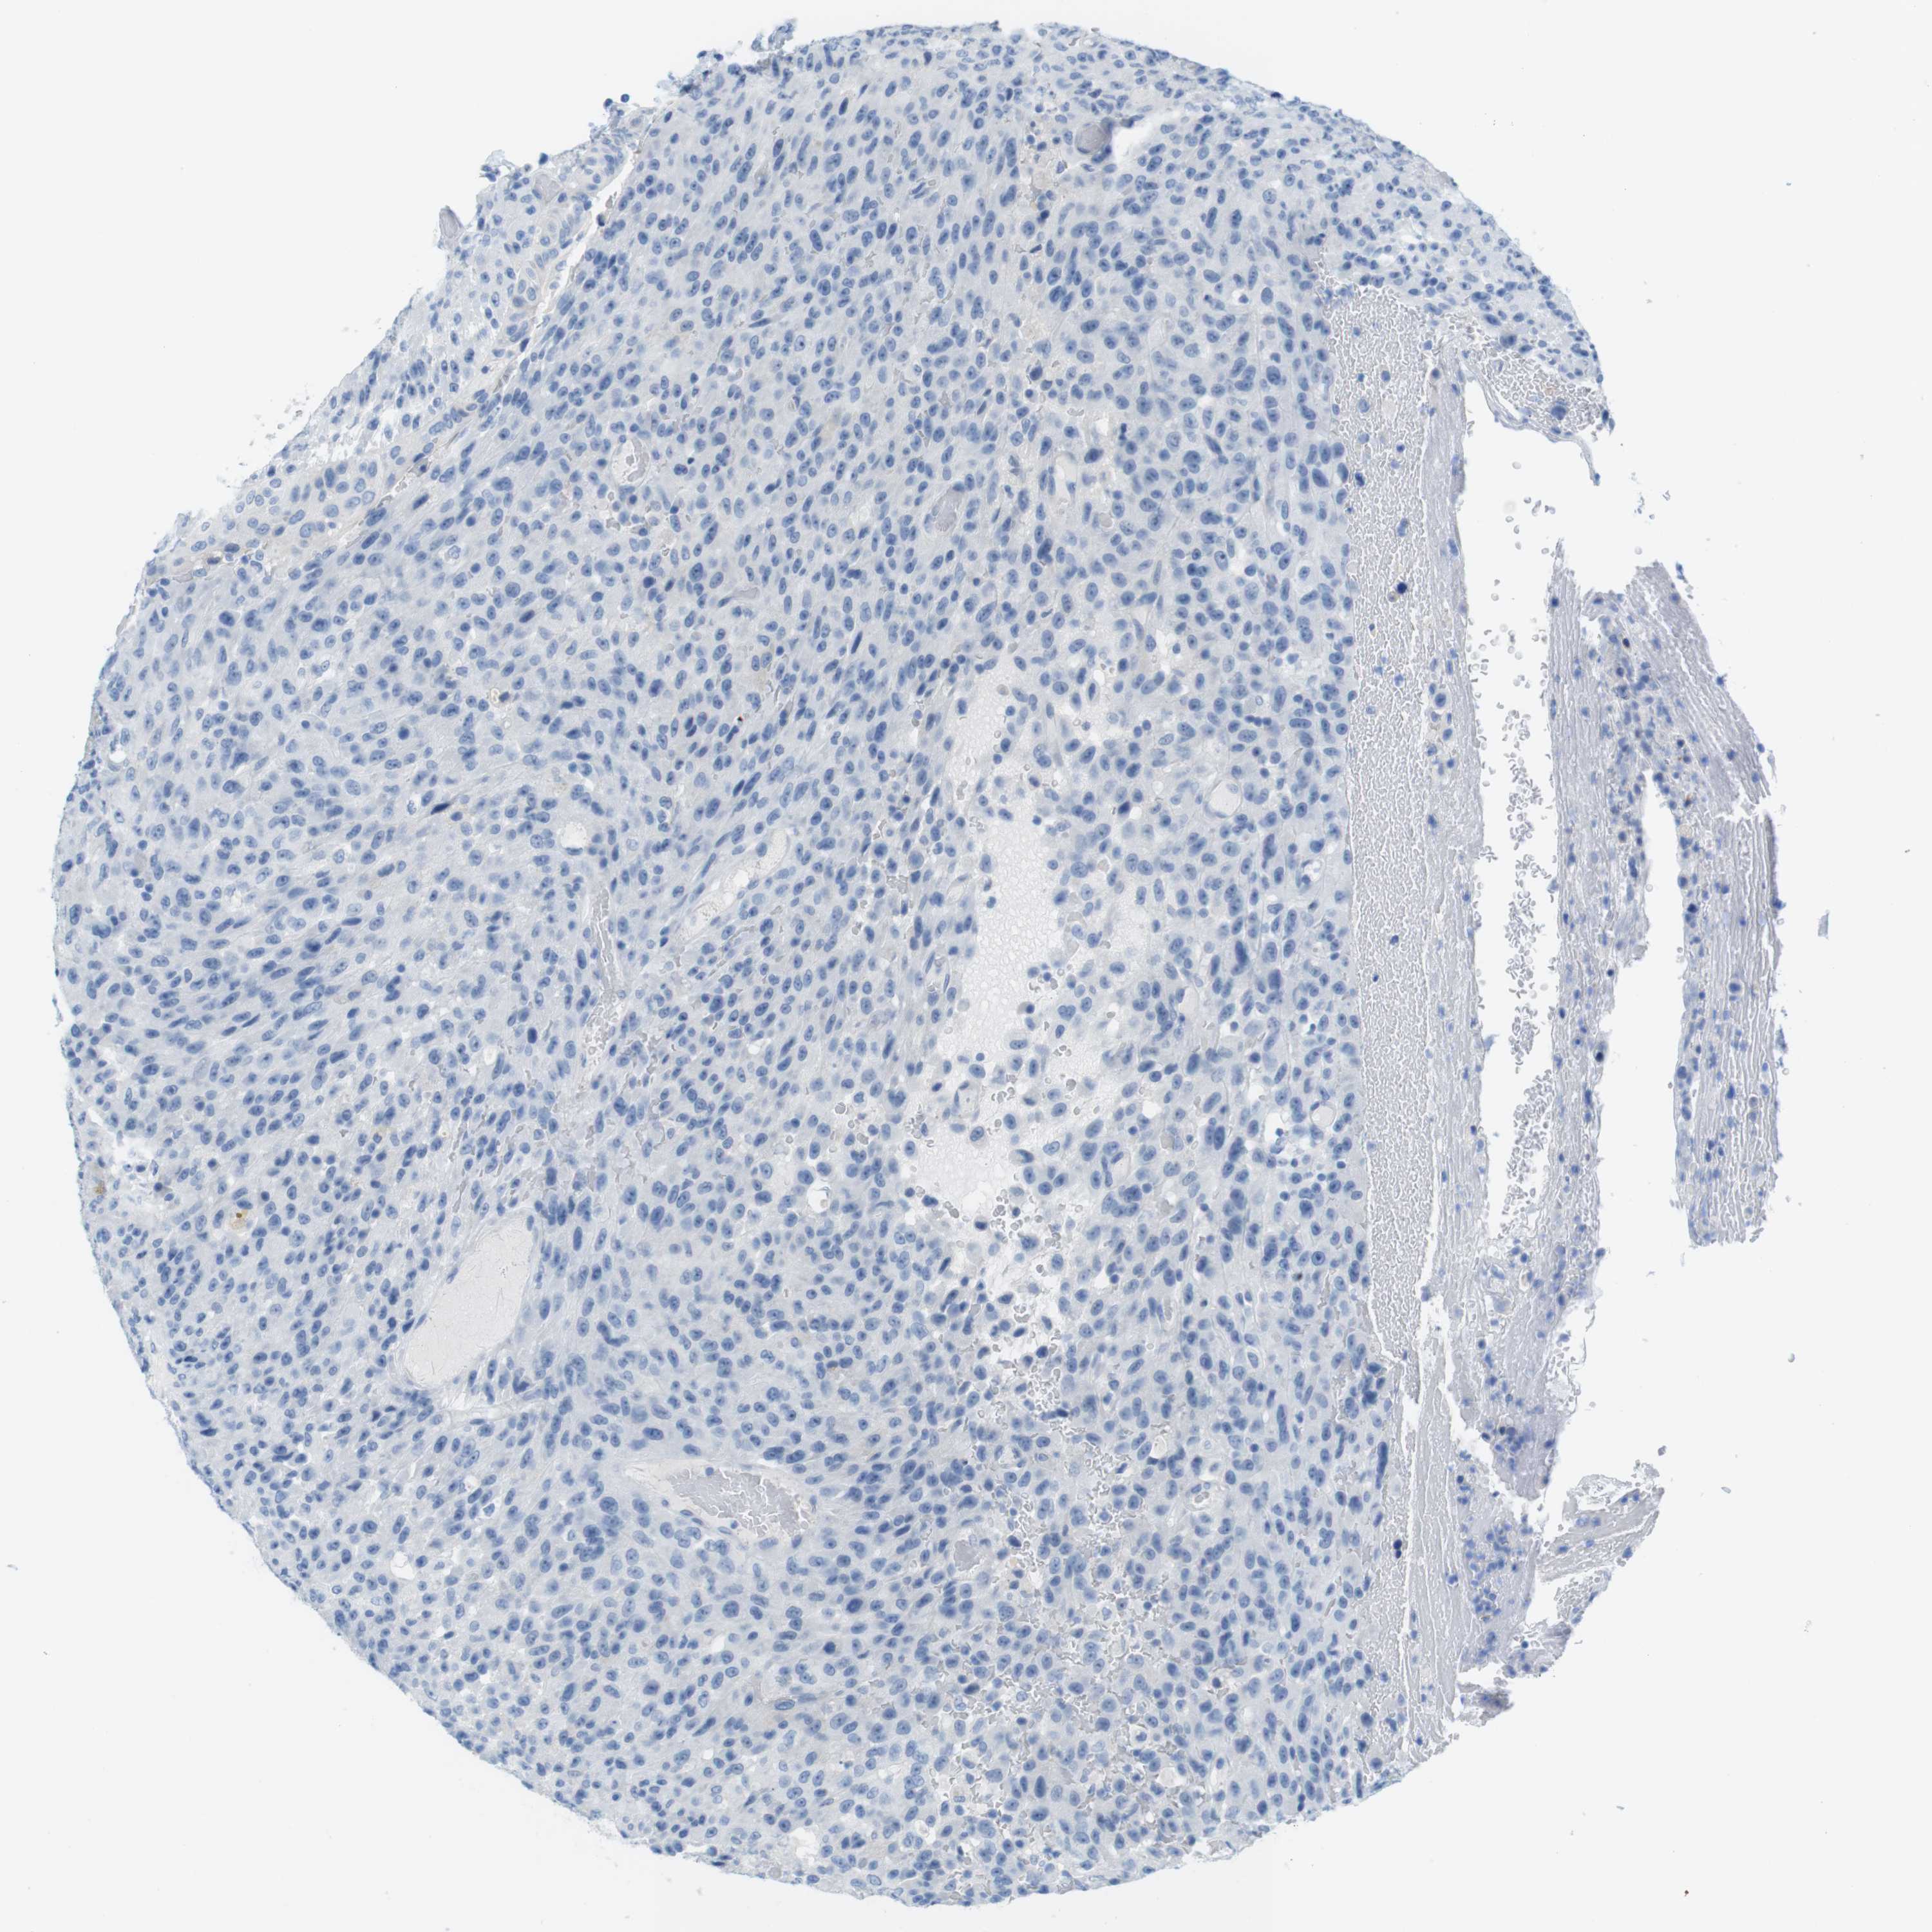

UROTHELIAL CANCER - Protein expressioni

A mouse-over function shows sample information and annotation data. Click on an image to view it in a full screen mode. Samples can be filtered based on level of antibody staining by selecting one or several of the following categories: high, medium, low and not detected. The assay and annotation is described here.

Note that samples used for immunohistochemistry by the Human Protein Atlas do not correspond to samples in the TCGA dataset.

Antibody stainingi

Antibody staining in the annotated cell types in the current human tissue is reported as not detected, low, medium, or high, based on conventional immunohistochemistry profiling in selected tissues. This score is based on the combination of the staining intensity and fraction of stained cells.

Each image is clickable and will lead to virtual microscopy that enables deeper exploration of all samples and also displays staining intensity scores, fraction scores and subcellular localization as well as patient and tissue information for each sample.

Antibody HPA013392

Antibody HPA015600

Antibody CAB004417

Staining

High

Medium

Low

Not detected

Intensity

Strong

Moderate

Weak

Negative

Quantity

>75%

75%-25%

<25%

None

Location

Nuclear

Cytoplasmic/membranous

Cytoplasmic/membranous,nuclear

Urothelial carcinoma, Low grade

Urothelial carcinoma, High grade